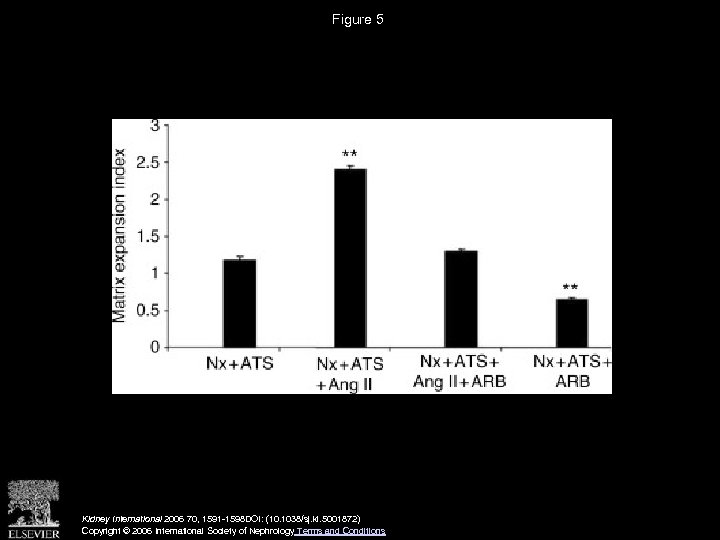

Figure 5 Kidney International 2006 70, 1591 -1598 DOI: (10. 1038/sj. ki. 5001872) Copyright © 2006 International Society of Nephrology Terms and Conditions